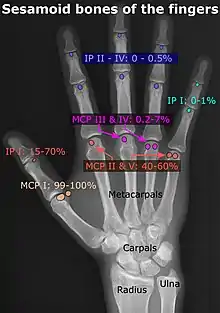

An accessory bone or supernumerary bone is a bone that is not normally present in the body, but can be found as a variant in a significant number of people. It poses a risk of being misdiagnosed as bone fractures on radiography.[2]

- Location and structure: Erica Chu, Donald Resnick. "MRI Web Clinic — June 2014: Sesamoid Bones: Normal and Abnormal". Retrieved 2017-11-04.

- Prevalences: Chen W; Cheng J; Sun R; Zhang Z; Zhu Y; Ipaktchi K; et al. (2015). "Prevalence and variation of sesamoid bones in the hand: a multi-center radiographic study". Int J Clin Exp Med. 8 (7): 11721–6. PMC 4565393. PMID 26380010. - ↑ "Poster Abstracts" (PDF). Association for Sports Medicine of Serbia (Udruženje za medicinu sporta Srbije). 2006. Retrieved 2017-11-03., citing: Natsis K.; Beletsiotis A.; Terzidis I.; Gigis P. "A study of the accessory bones of the foot. Incidence in the Greek population-clinical significance" (PDF).